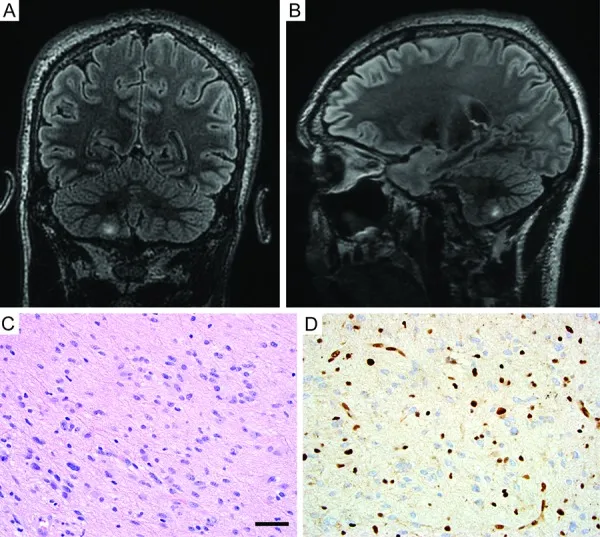

图3. 右小脑切除的弥漫性星形细胞瘤的影像学与组织学特征。

A, B: T2/FLAIR加权磁共振像显示右小脑半球高信号肿块病变(冠状位A;矢状位B)。C: 苏木精-伊红染色切片显示弥漫性胶质瘤,由肿瘤性纤维性星形细胞组成,细胞核细长、不规则、深染,浸润于小脑皮层下白质。D: ATRX蛋白免疫组化染色显示肿瘤细胞染色缺失,而包绕其中的非肿瘤性神经元及内皮细胞染色完整,符合体细胞ATRX缺失。比例尺:40微米。

为进一步评估患者,亦进行了脊髓磁共振成像,结果显示右侧C6-7神经孔内有一膨胀性、对比强化的肿块沿C7神经根走行,符合周围神经鞘瘤表现(图4)。左额开颅术后1个月,患者接受了右小脑病变切除术。病理显示为弥漫性星形细胞瘤,由肿瘤性纤维性星形细胞组成,细胞核细长、不规则、深染,浸润于小脑皮层下白质及内颗粒层(图3C)。肿瘤细胞ATRX免疫染色缺失,而包绕其中的非肿瘤性神经元及内皮细胞染色完整,符合ATRX缺失(图3D)。免疫组化检测显示肿瘤细胞IDH1-R132H及组蛋白H3-K27M突变蛋白阴性。Ki67标记指数约5%的肿瘤细胞阳性。诊断为弥漫性星形细胞瘤,WHO II级。考虑到显著的家族史以及存在多种组织学类型不同的脑肿瘤和一处周围神经鞘瘤,建议进行基因组检测。